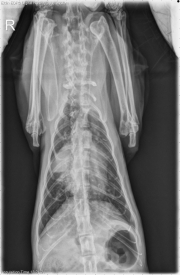

Today’s case is a 12 year old male neutered Domestic Shorthair cat with anorexia and increased respiratory effort for 3 days. What is your radiographic diagnosis?

DV Thorax

The cardiac silhouette is markedly enlarged on all projections. There is a bulge in the region of the carina and at the base of the right middle lung lobe, which is increased in opacity. The pulmonary vasculature is enlarged. There is a diffuse bronchointerstitial pattern throughout the lungs, and there is increased opacity in the region of the left cranial lung lobe.

Cardiomegaly is most likely due to cardiomyopathy due to primary heart disease or hyperthyroidism. The mass effect in the right cranial thorax may be a pulmonary mass with secondary right middle lobe atelectasis or an enlarged cardiac chamber. The diffuse bronchointerstitial pattern is consistent with lower airway disease, which may have infectious and noninfectious inflammatory components. The opacity in the left cranial thorax may be due to effusion or a cranial thoracic mass.

• Hypertrophic cardiomyopathy

• Hyperthyroidism

• Ruled out thoracic mass by ultrasound examination – enlarged atrium

• No abnormalities in left cranial thorax